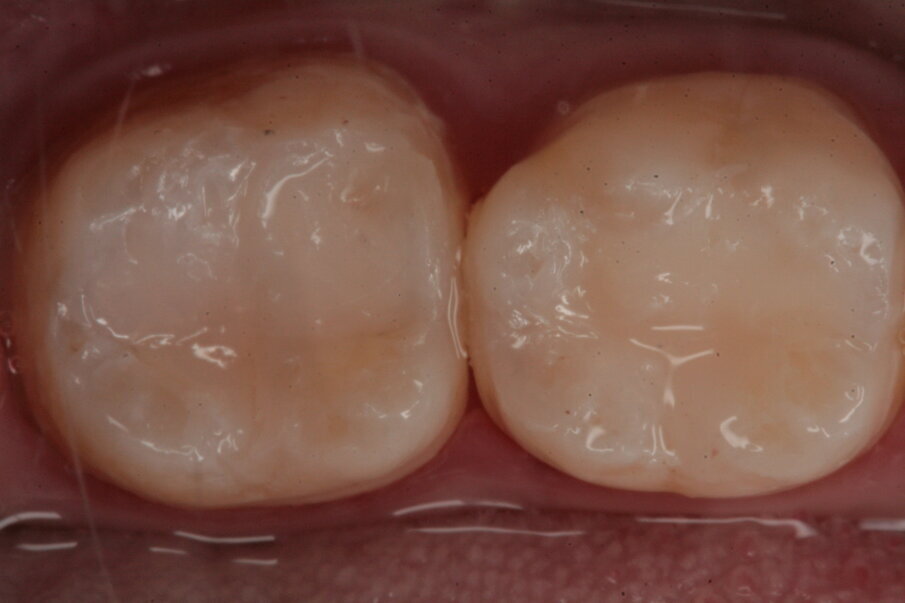

Gli elementi da trattare, 36 e 37, all’esame obiettivo presentano leggeri solchi intaccati dal processo carioso (Figg. 19, 20); clinicamente la dentina viene interessata perciò si procede al restauro mediante due masse, una dentinale e una smaltea (Figg. 21, 22).

Fig. 19_Restauro presente nell’elemento 37 e solchi interessati dal processo carioso dell’elemento 36.

Fig. 20_Isolamento del campo operatorio.

Fig. 22_Visione finale del restauro.